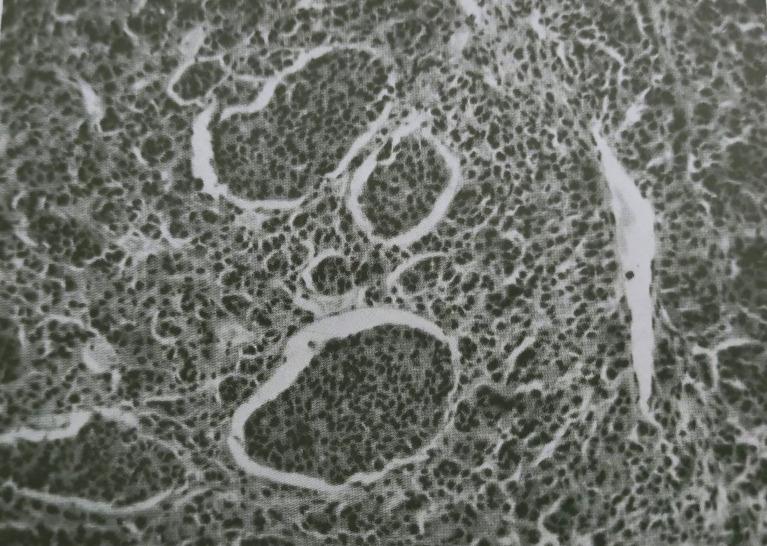

Uveal melanoma (UM) is the most frequently found primary intraocular tumor, although it accounts for only 5% of all melanomas. Despite novel systemic therapies, patient survival has remained poor. Indeed, almost half of UM patients develop metastases from micro-metastases which were undetectable at diagnosis. Genetic analysis is crucial for metastatic risk prediction, as well as for patient management and follow-up. Several prognostic parameters have been explored, including tumor location, basal dimension and thickness, histopathologic cell type, vascular mimicry patterns, and infiltrating lymphocytes. Herein, the Authors review the available literature concerning cytogenetic prognostic markers and biochemical pathways correlated to UM metastasis development.

葡萄膜黑色素瘤(UM)是最常见的原发性眼内肿瘤,尽管它仅占所有黑色素瘤的5%。尽管有了新的全身治疗方法,但患者的生存率仍然很低。事实上,几乎一半的UM患者会从诊断时无法检测到的微转移发展为转移。基因分析对于转移风险预测以及患者管理和随访至关重要。已经探索了几个预后参数,包括肿瘤位置、基底尺寸和厚度、组织病理学细胞类型、血管拟态模式和浸润淋巴细胞。在此,作者回顾了有关细胞遗传学预后标志物和与UM转移发展相关的生化途径的现有文献。